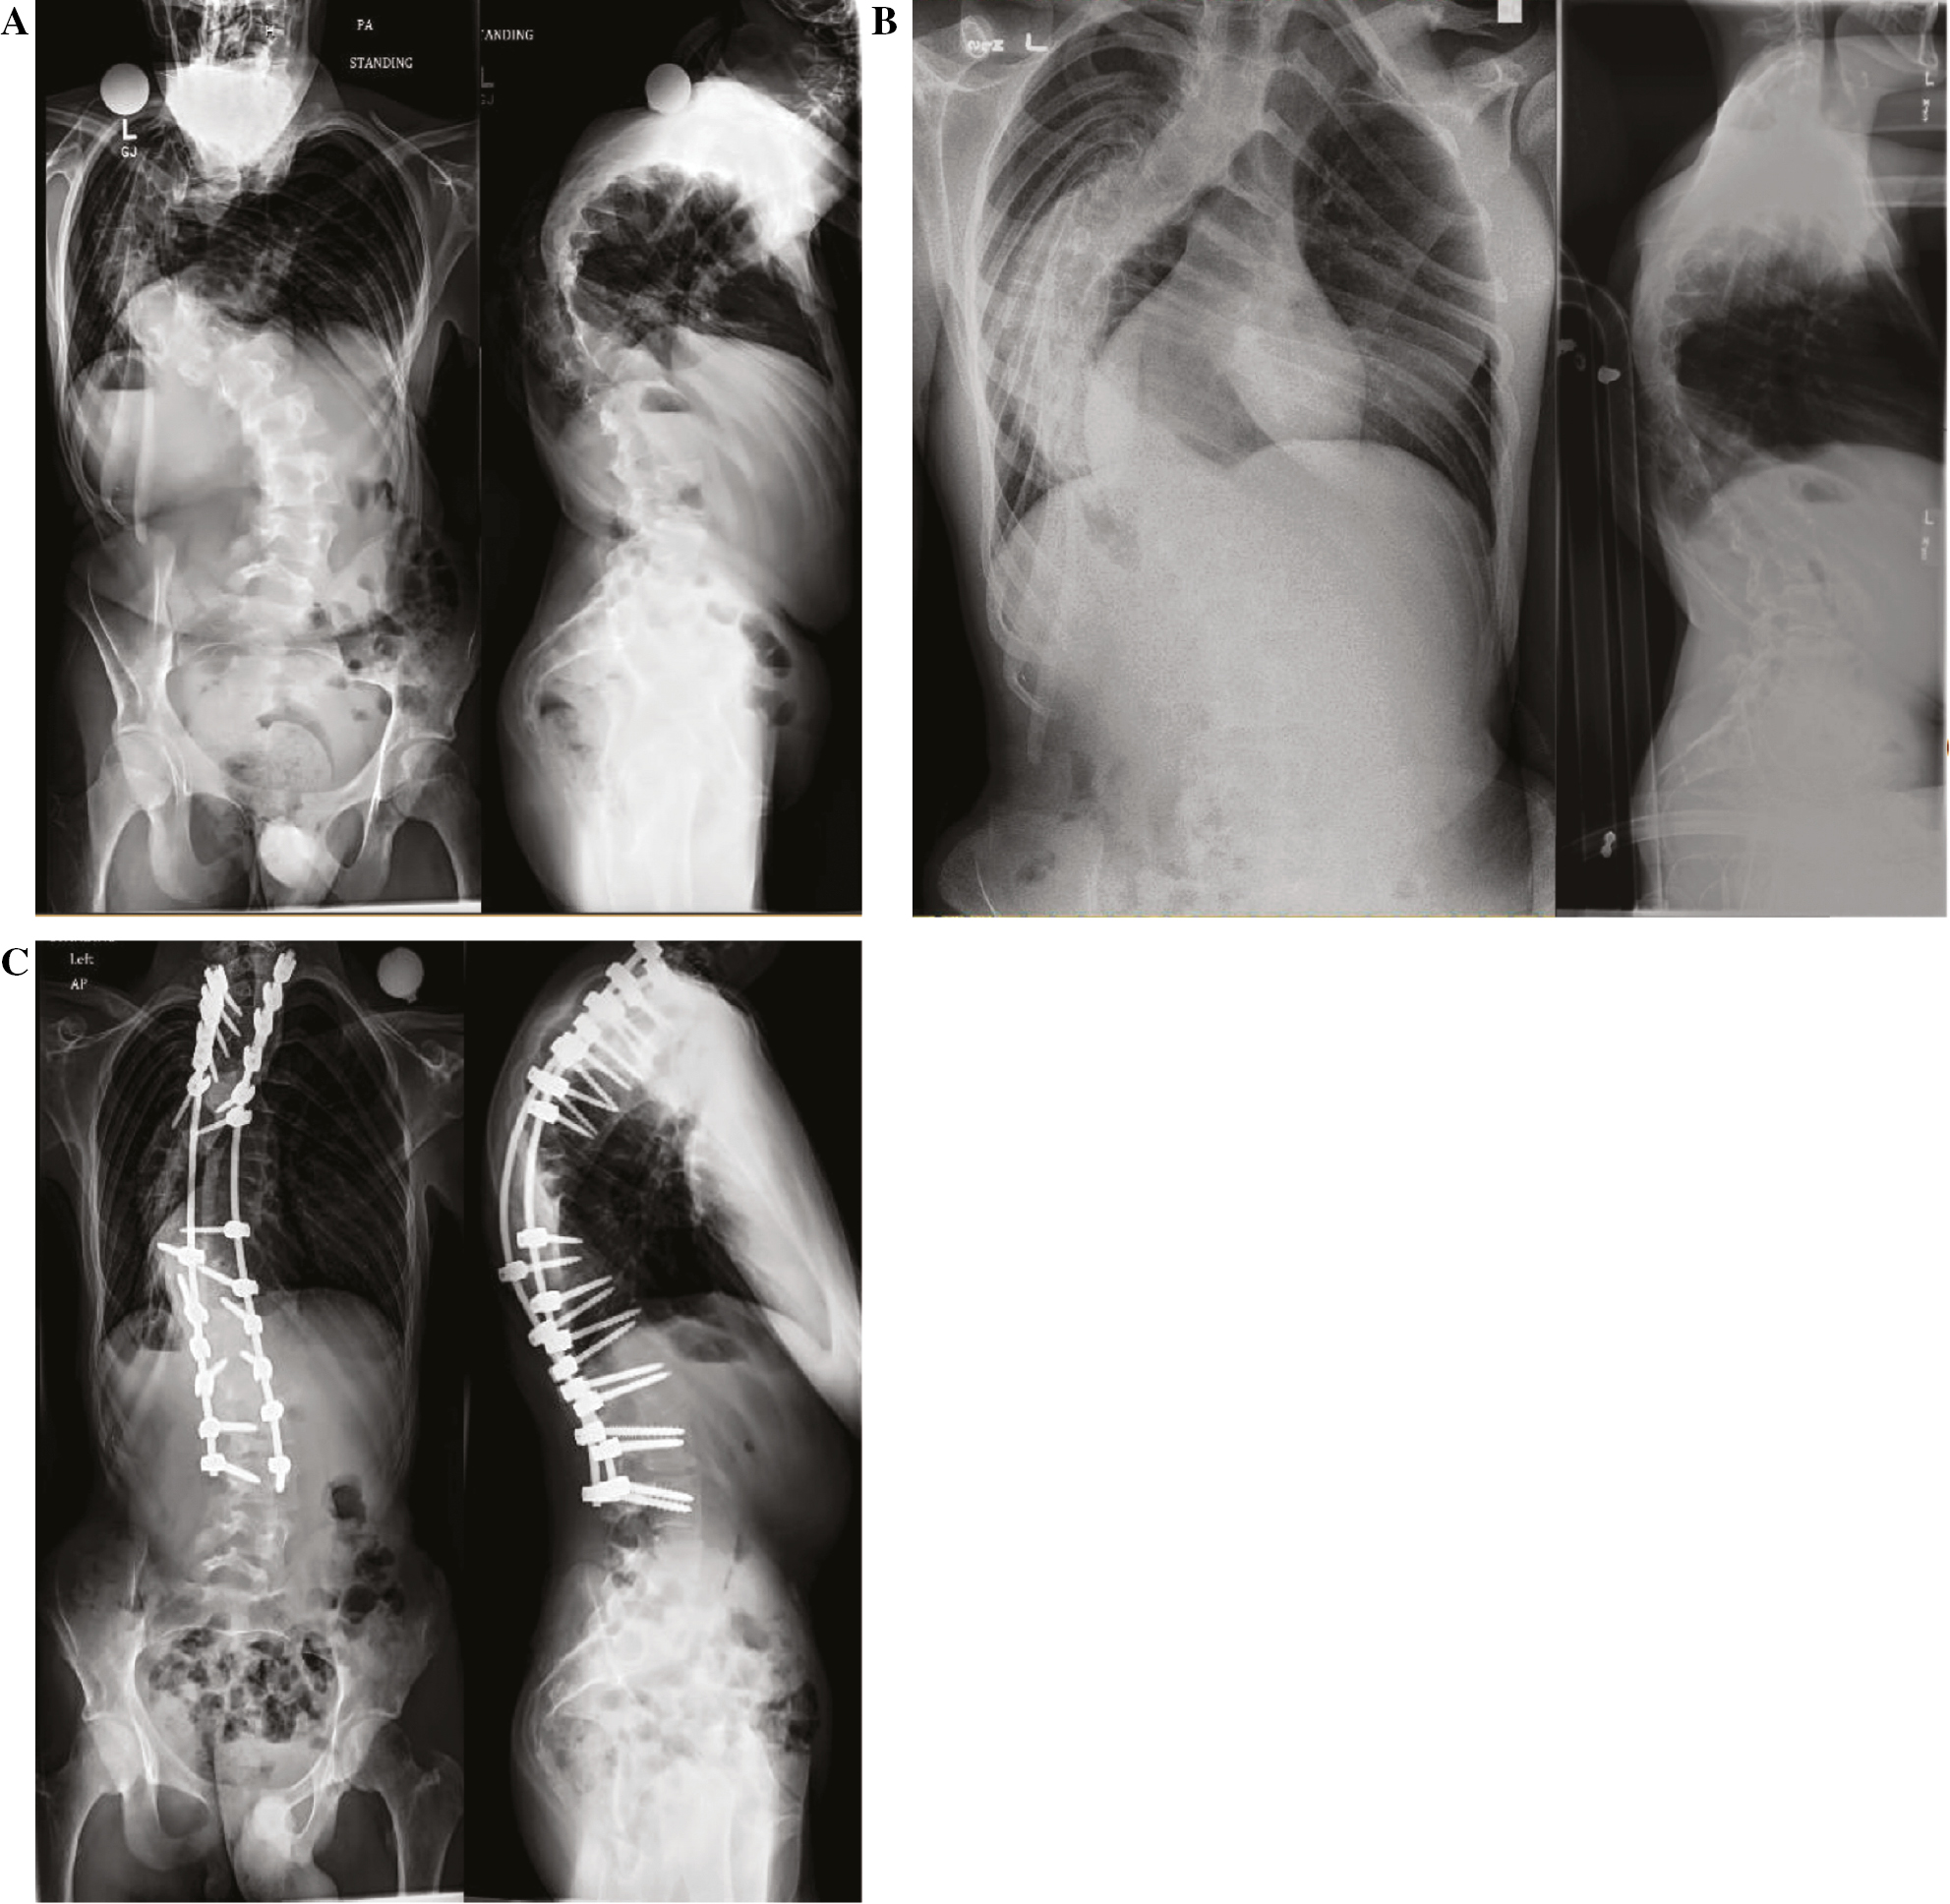

Larger kyphosis also increases the possibility of neurological injury, especially in the setting of congenital curves or revision surgery.20,23–26 Larger curves may benefit from preoperative halo-gravity traction to allow the spinal column, including the spinal cord, to undergo slow and gently stretching while the patient is awake and can provide regular neurological examinations27 (Figure 3).

Figure 3. (A) A 12 year old male with Soto syndrome, a coronal curve of 113°, sagittal curve of 103° and a T-DAR of 24.2 (C-DAR = 11.3 S-DAR = 12.9). (B) He was treated with 6 weeks of halo gravity traction, taking his coronal curve down to 84° and his sagittal curve to 68°. (C) He was then treated with PSF without IONM changes.